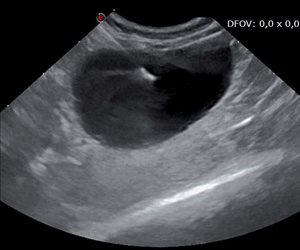

Un contrôle échoguidé facilite la réalisation du geste. La vessie est repérée par échographie ; son niveau de remplissage est estimé.

Photo 3B

L’aiguille est introduite crânialement à la sonde échographique, dans le même plan que celle-ci et selon le même principe que précédemment.

Photo 3C

L’échographie permet de visualiser le trajet de l’aiguille et de confi rmer la présence de son extrémité dans la lumière vésicale.